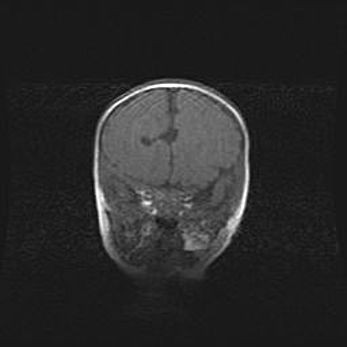

Подострая гематома правой гемисферы мозжечка.

Наружная гидроцефалия.

Возраст: 15 дней

Вес: 3100 г

Пол: женский

Окружность головы: 37 см

Срок гестации: 35-36 недель

При открытой наружной форме гидроцефалии у новорожденных расширяются и переполняются субарахноидные пространства.

Кровоизлияния в мозжечок имеют две клинико-анатомические формы: полушарные гематомы и кровоизлияния в червь.

К появлению этой патологии может привести: повреждения головного мозга, возникающие в результате асфиксии и гипоксии плода при беременности, или травмы во время родов. Редко гематома мозжечка может быть результатом первичной коагулопатии и сосудистой мальформации, диссеминированном внутрисосудистом свертывании, изоиммунной тромбоцитопении.